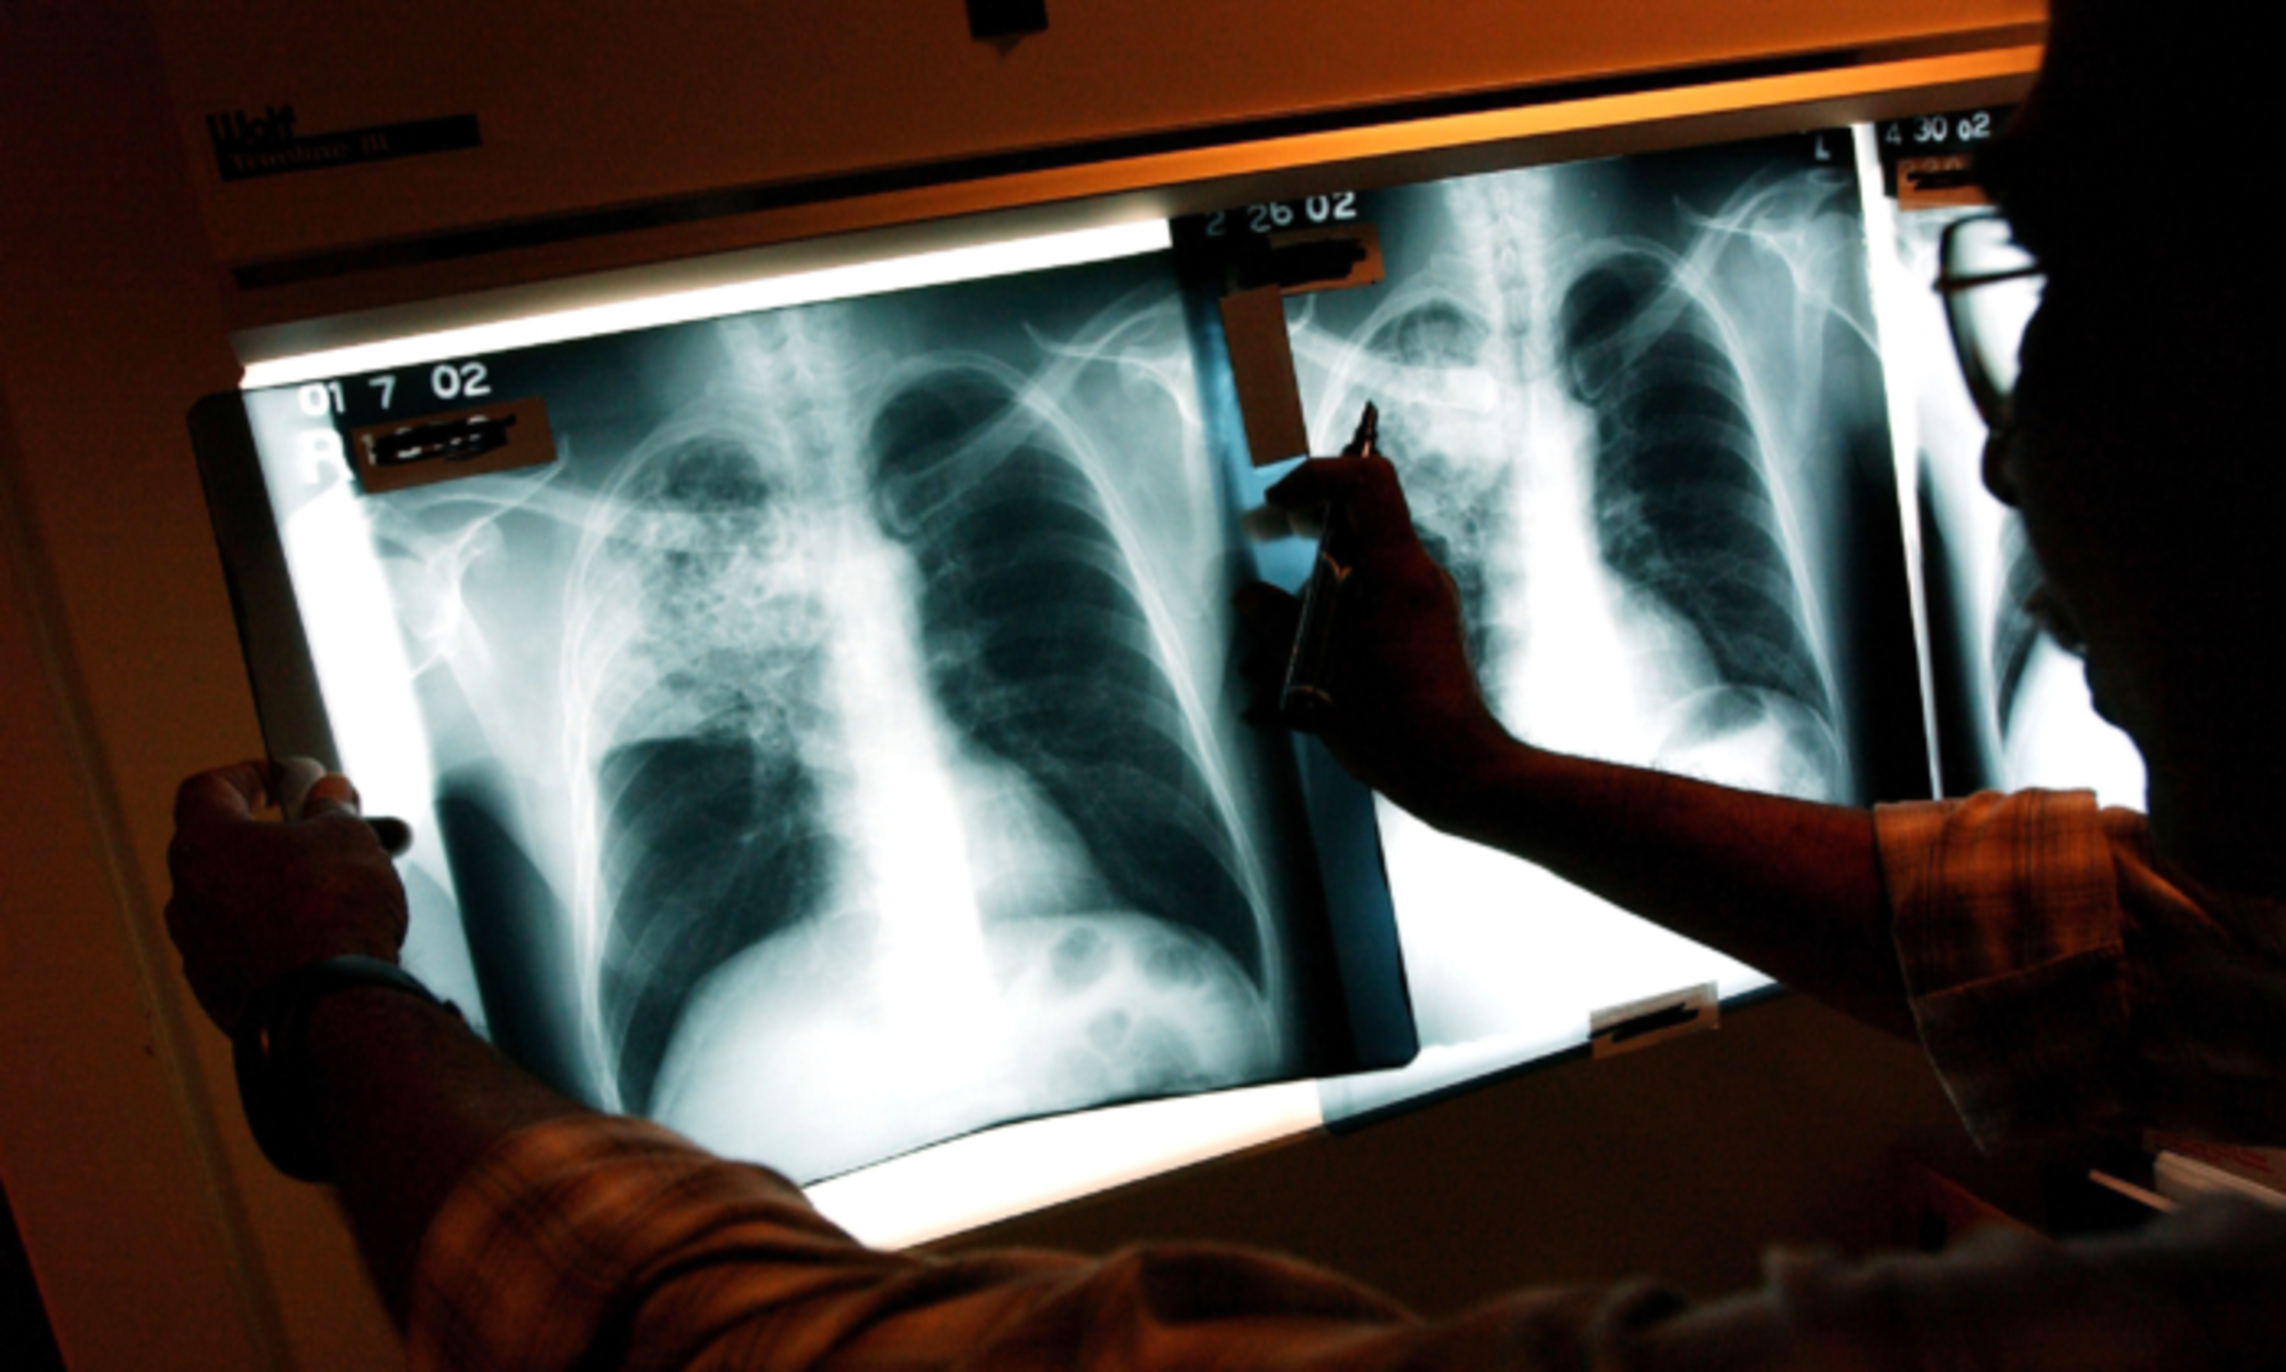

Deadly Lung Disease Cases Surge to 10-Year High, Children Most Affected: CDC

U.S. cases of tuberculosis, a deadly infectious disease that typically strikes the lungs, have soared to their highest level in a decade, according to the Centers for Disease Control and Prevention (CDC), with the largest relative increase among children. After 27 years of declining tuberculosis rates in the United States, cases of the disease started to climb again in 2020—and they’ve continued to rise every year since, the CDC said in a March 28 report. In 2023, tuberculosis case counts jumped by 1,295 from the prior year to 9,615, the agency said. This represents an increase of 16 percent and is the highest level since 2013....